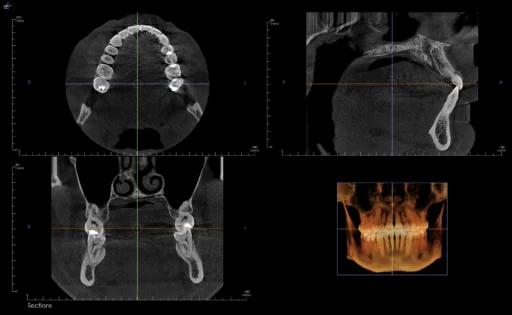

• small volume CBCT scans to aid diagnosis and planning

We use specialized equipment, including: Operating microscope (Zeiss Extaro) to aid in visualisation and illumination of the canal structures. 3-D small volume CBCT (Kavo) to aid diagnosis and planning